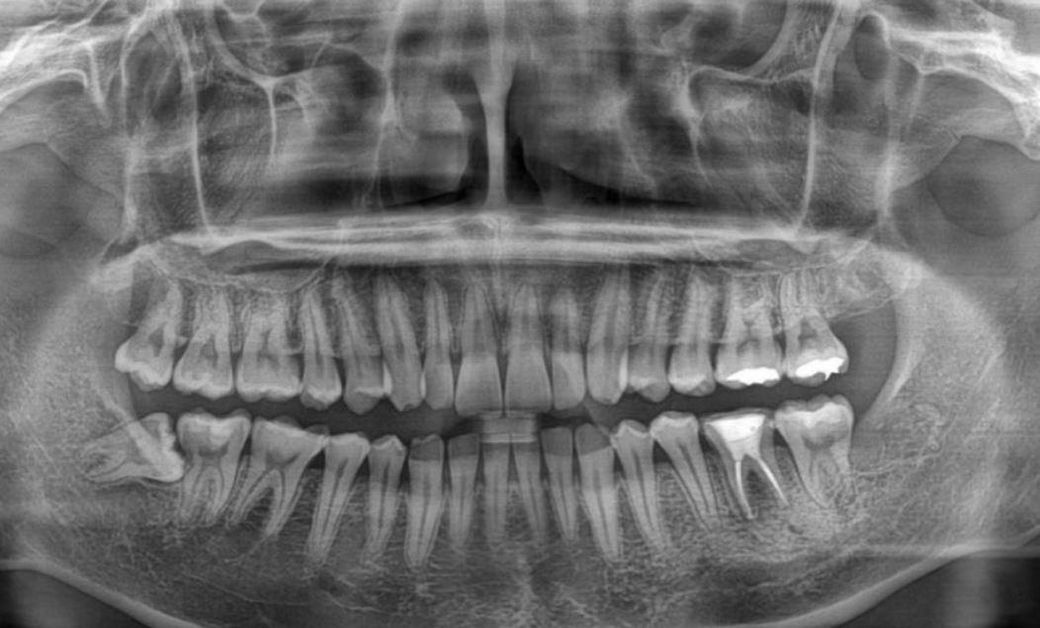

첫번째 사진은 신경치료 받기 전 사진이고 두번째 사진은 신경치료를 받은 후의 사진입니다.

Q2. 치아 뿌리에 금이 가더라도 파노라마 사진에서 염증의 크기가 줄어들까요? 첫번째 사진과 두번째 사진을 비교해봤을 때, 언뜻 보기에 염증크기가 줄어든 거 같아서 여쭤봅니다.

• 2번 째 사진

2. 사진상 염증 개선되고 있습니다. 증상 좀 더 지켜보시죠